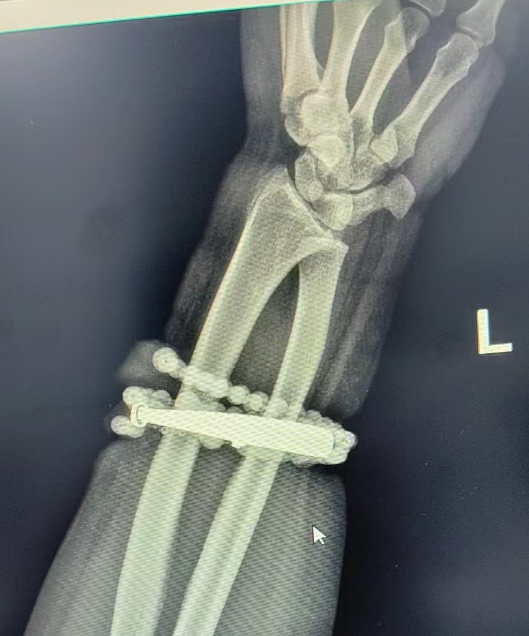

33岁的龚女士(化名)

来到福建省宁德市闽东医院就诊

她手腕上的银手镯和串珠戴了近十年

几乎从未摘下

随着体重上涨,手镯和串珠

竟有一部分“长”进了手腕里

如果不尽快取下首饰

可能会影响龚女士手臂甚至危及生命

万幸经过手术

医生们成功将首饰完整剥离出来

目前龚女士恢复良好,已顺利出院